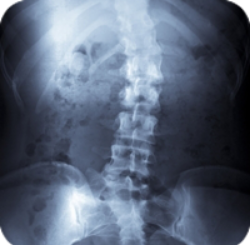

Scoliosis is derived from the Greek term meaning curvature. People with scoliosis have a sideways curve in their spine that makes an "S" or "C" shape. The vertebrae can rotate at the thoracic level of the spine causing this curve and resulting in a hump near the rib cage. If the curve is more than 60 degrees it is considered serious. Usually this curve makes the waist or shoulders uneven. And unlike the normal curvature of the spine, adjusting your posture will not correct the problem.

In some instances, the degenerative diseases of the spine can cause scoliosis. Osteoporosis is when the bones soften and usually occurs in older people. This softening can cause the vertebrae to bend and shape the curve causing scoliosis or kyphosis (round back). If not treated properly, severe back pain, deformity, and difficulty breathing can be some symptoms that will arise.